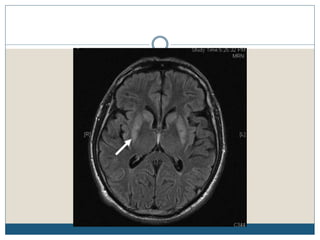

Typical MRI lesions

 Trident shaped / spreading bushfire pattern in central pons

 Signal characteristics of affected region include:

 T1: mildly or moderately hypointense

 T2: hyperintense, sparing the periphery and corticospinal tracts

 FLAIR: hyperintense

 DWI: hyperintense

 ADC: signal low or signal loss

 T1 C+ (Gd): usually there is no enhancement

 Radiologic findings do not improve over time, despite complete or nearly complete

clinical recovery

Typical MRI lesions Trident shaped / spreading bushfire pattern in central pons  Signal characteristics of affected region include:  T1: mildly or moderately hypointense  T2: hyperintense, sparing the periphery and corticospinal tracts  FLAIR: hyperintense  DWI: hyperintense  ADC: signal low or signal loss  T1 C+ (Gd): usually there is no enhancement  Radiologic findings do not improve over time, despite complete or nearly complete clinical recovery